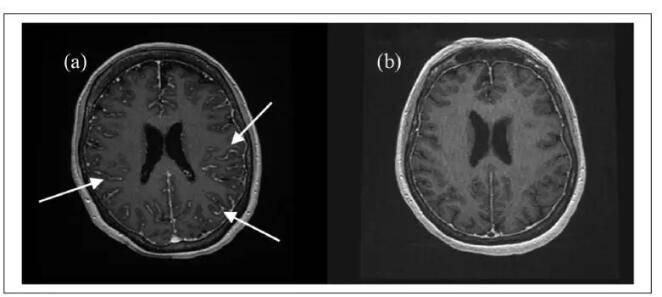

氯硝西泮使用后,患者的眼睑活动及面部表情僵硬情况得到改善。脑MRI显示弥漫性脑膜增强(下图a),考虑是自身免疫性炎症反应,遂将地塞米松剂量增加到6mg/8小时。7天后,临床症状改善较小,但是脑脊液检查看到明显变化(中性粒细胞9mcL,蛋白质302mg/dL,IgG/白蛋白比值及IgG合成率也正常)。激素增量后第8天的MRI显示脑膜病变缓解(下图b),脑电图显示无癫痫。